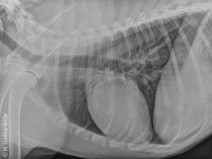

• Travaux pratiques de radiographie abdominale

Le GEIM vous propose une séance de travaux pratiques de radiographies sur l’abdomen. Tous les aspects sont abordés sous la forme de TP de lecture de radiographies numériques sur station de travail Athena sur tablettes

• Travaux pratiques de radiographie / Le Thorax

Le GEIM vous propose une séance de travaux pratiques de radiographies sur le thorax. Tous les aspects sont abordés sous la forme de TP de lecture de radiographies numériques sur station de travail Osirix.